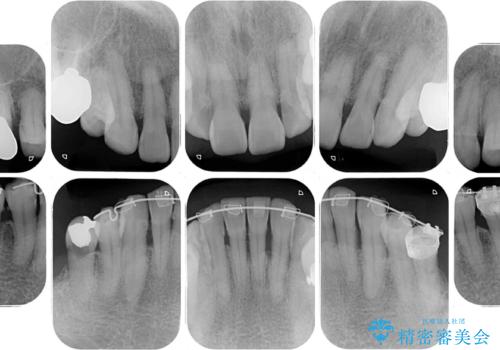

- インプラント治療を前提に下顎の部分矯正を始めたものの、そのまま長い間放置しているとのことで来院された患者様です。

全体的に歯肉が腫れており、歯周病により抜歯をしなければならない歯がある状態でした。

矯正治療を仕上げ、必要に応じて歯周外科処置を行い、適宜インプラントを埋入しながら咬み合わせを回復させていくこととしました。